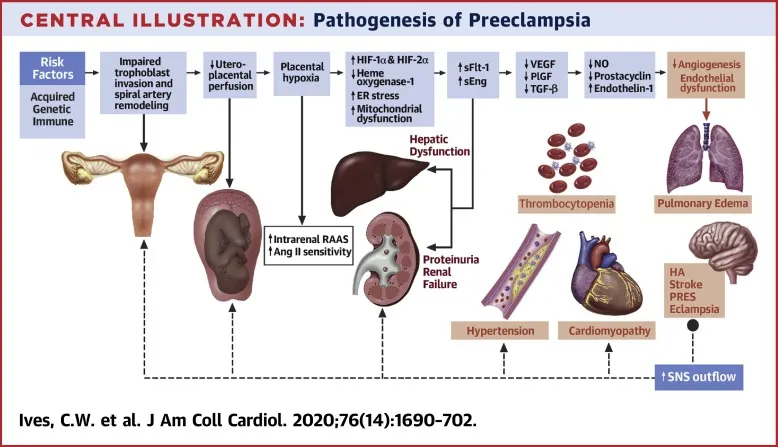

HRP: Hypertensive Disorders - Pressure Cooker Situations

- Classification:

- Chronic HTN: BP ≥140/90 mmHg <20 wks.

- Gestational HTN (GHTN): BP ≥140/90 mmHg >20 wks, no proteinuria.

- Preeclampsia (PE): GHTN + Proteinuria (≥300mg/24h / PCR ≥0.3).

- Severe Features: BP ≥160/110 mmHg OR end-organ dysfunction (platelets <100k/µL, LFTs ↑↑, Creat >1.1mg/dL, pulm edema, CNS sx).

- Eclampsia: PE + Seizures.

- HELLP: Hemolysis, Elevated Liver enzymes, Low Platelets.